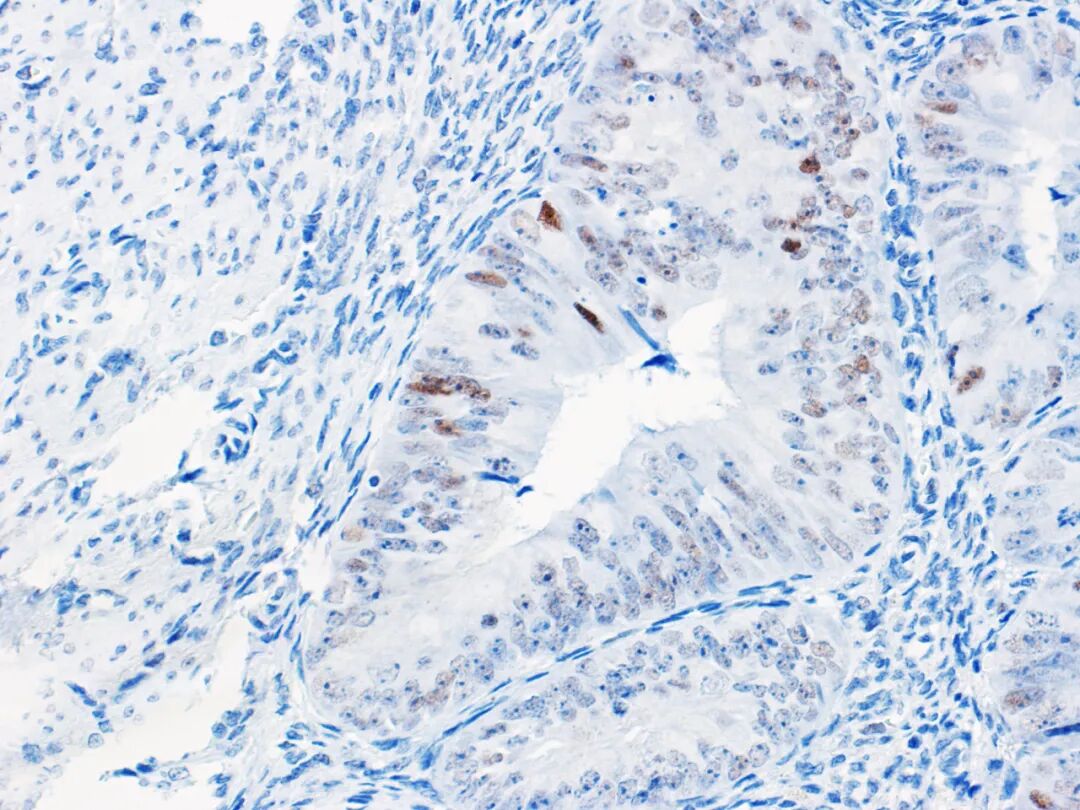

p53免疫组化可预测子宫内膜癌中Tp53基因突变情况(如图4、图5所示)。子宫内膜癌的异质性使大概5%的病例出现判读困难,且这部分病例多数是伴有POLE突变或MMR缺陷。

图4.子宫内膜癌-野生型p53正常表达

Tp53基因突变是高拷贝数型的特征。大量体细胞拷贝数异常是子宫内膜浆液性癌和被描述为“浆液样”的子宫内膜样癌的特征。研究发现,p53突变型的子宫内膜样癌3级的预后比子宫内膜样癌3级差,对化疗可能敏感。拷贝数高型子宫内膜癌并且Tp53基因突变可对应于 Bokhman描述的II型子宫内膜癌,而拷贝数低型子宫内膜癌对应于I型子宫内膜癌。POLE突变/突变型p53或MMR缺陷/突变型p53的子宫内膜癌患者的预后结果好于仅有Tp53基因突变的子宫内膜癌患者。p53 IHC现在在检测子宫内膜癌的高拷贝数型、浆液样分子亚型方面比测序更具有显著优势。外阴鳞状细胞癌有三种分子类型:HPV相关、HPV无关/Tp53基因突变、HPV无关/Tp53基因正常。精确评估p53情况对于HPV无关的外阴鳞状细胞癌分类非常关键。最近有研究表明,根据专门针对外阴鳞状细胞癌的p53免疫组化解读标准,其免疫组化结果可以准确预测Tp53基因突变状态。子宫间质性肿瘤发现有特异性基因易位或分子改变,具体如伴YWHAE-NUTM2A/B融合、ZC3H7B-BCOR融合、BCOR内部串联重复的高级别子宫内膜间质肉瘤,伴ALK重排的炎性肌纤维母细胞肿瘤,NTRK重排的梭形细胞肿瘤。尽管某些免疫组化可用于缩小鉴别诊断的范围,但这类肿瘤一般需分子检测证实。平滑肌肉瘤及子宫的多形性未分化肉瘤大部分都有Tp53基因突变。因此,免疫组化p53的作用就是筛选出无特异性异位、有Tp53基因突变的子宫间质肿瘤行进下一步分子检测。